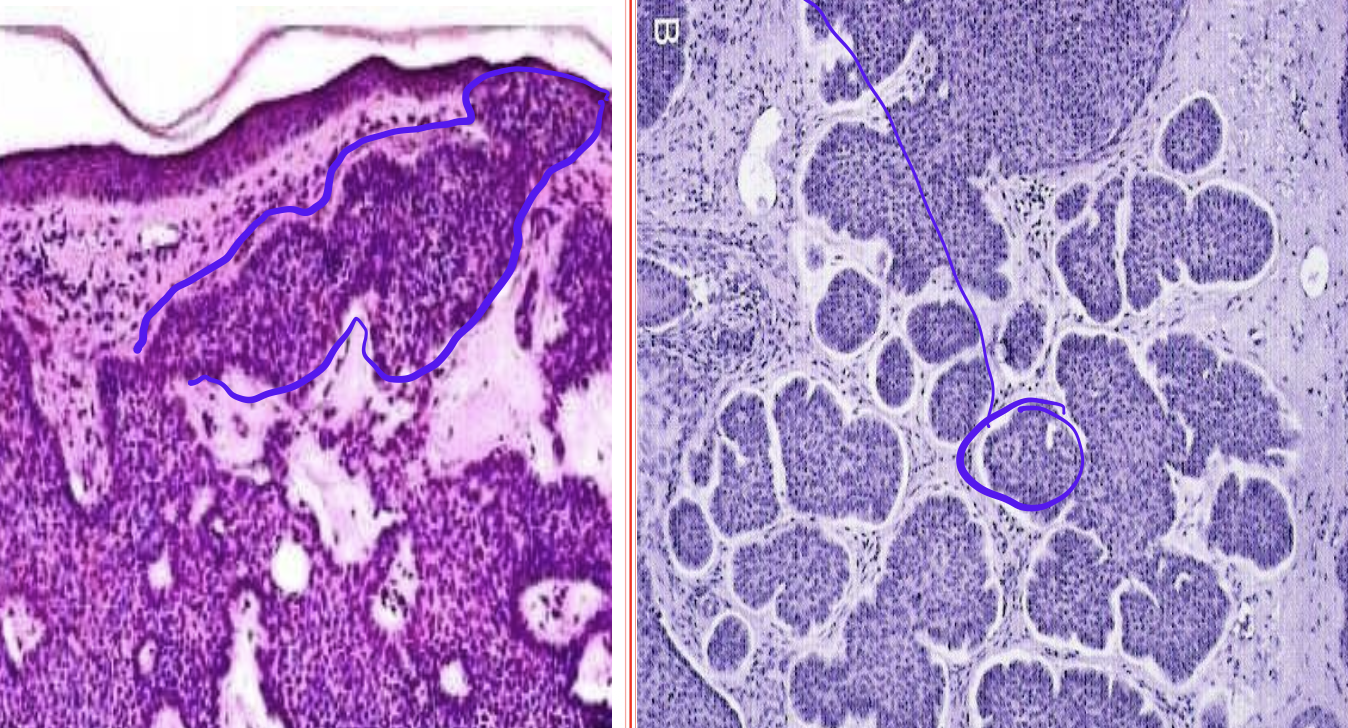

Identify the organ and the diagnosis in this format: diagnosis, organ

carcinoma in situ, cervix